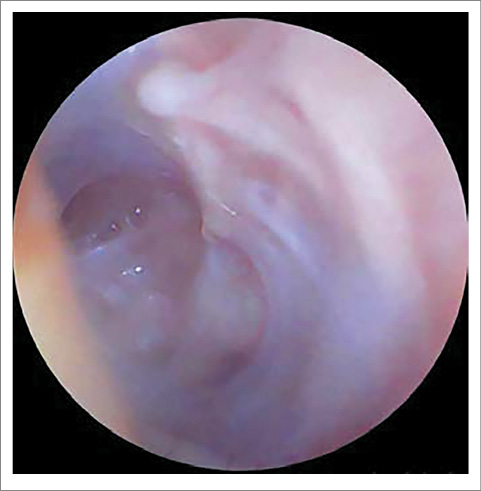

ЛОР-статус на момент поступления: AD – околоушная, заушная область не изменена, при пальпации безболезненна. При отоскопии: наружный слуховой проход несколько сужен из-за отечности стенок, в просвете визуализируется скудное гнойное отделяемое. Определяется тотальная перфорация БП, слизистая медиальной стенки барабанной полости утолщена, покрыта серо-белым субстратом (фибрин? некротические ткани?); рис. 1.

Рис. 1. Отоскопическая картина справа при поступлении: тотальная перфорация БП, слизистая медиальной стенки барабанной полости утолщена, покрыта серо-белым субстратом (фибрин? некротические ткани?).